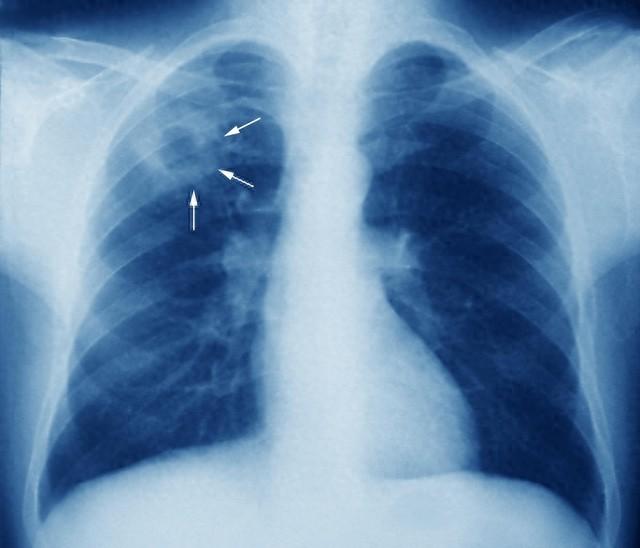

在医学影像学中,肺部“磨玻璃样改变”一直是一个备受关注的话题。这种改变在CT扫描上表现为肺部区域的密度轻度增高,但其中的血管和支气管结构仍可见,呈现出一种类似磨砂玻璃的外观。

具体来说,当呼吸道受到细菌、病毒等病原体的侵袭时,肺泡内会发生炎症反应,导致少量组织碎片、渗出液等聚集在肺泡内。这些物质在CT扫描下呈现出密度增高、边缘模糊的影像,即所谓的“磨玻璃样改变”。

在影像学特征上,“磨玻璃样改变”表现为肺部广泛或局灶性的密度增高区,边缘模糊,支气管和血管纹理可透过,而“磨玻璃样结节”则表现为局灶性的密度增高影,直径通常在3cm以下。这些特征有助于在影像学检查中初步区分两者。

结果显示,“磨玻璃样改变”患者的病变区域广泛,涉及多个肺叶或肺段,而“磨玻璃样结节”患者的病变区域则相对局限,多位于肺上叶或肺外带。